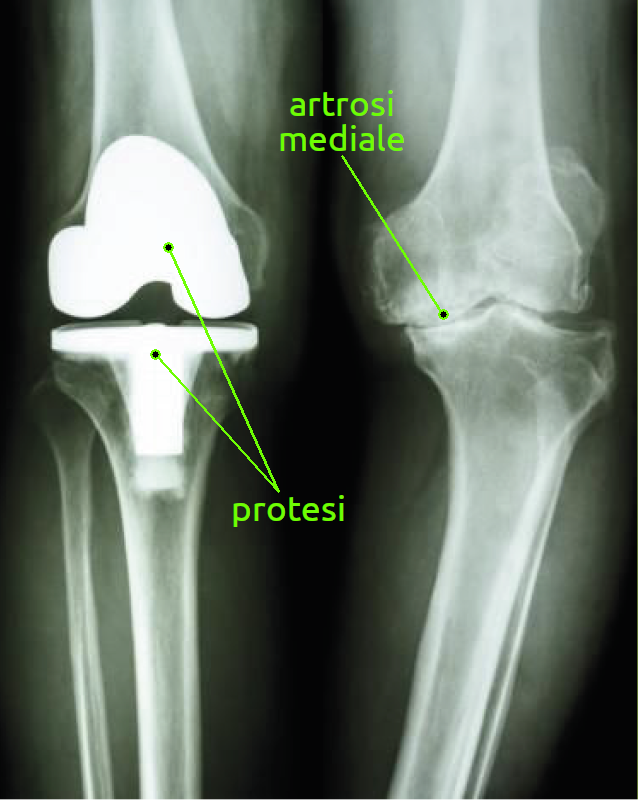

Spesso nel ginocchio artrosico è compresente una alterazione dell'asse femoro-tibiale con due varianti: